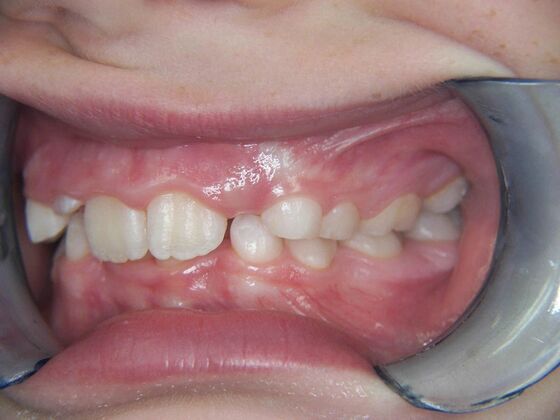

Patient is 9 years old and presents with 100% overbite and blocked out upper and lower lateral incisors. Both upper central incisors are palatally inclined causing a lack of space available for most anterior teeth. Advised her parents that she needs Phase I Interceptive Orthodontic treatment to provide room for all upper and lower front teeth. Phase I treatment was begun and finished, then began Phase II treatment shortly thereafter to finalize case. Removable retainer were fabricated for retention.